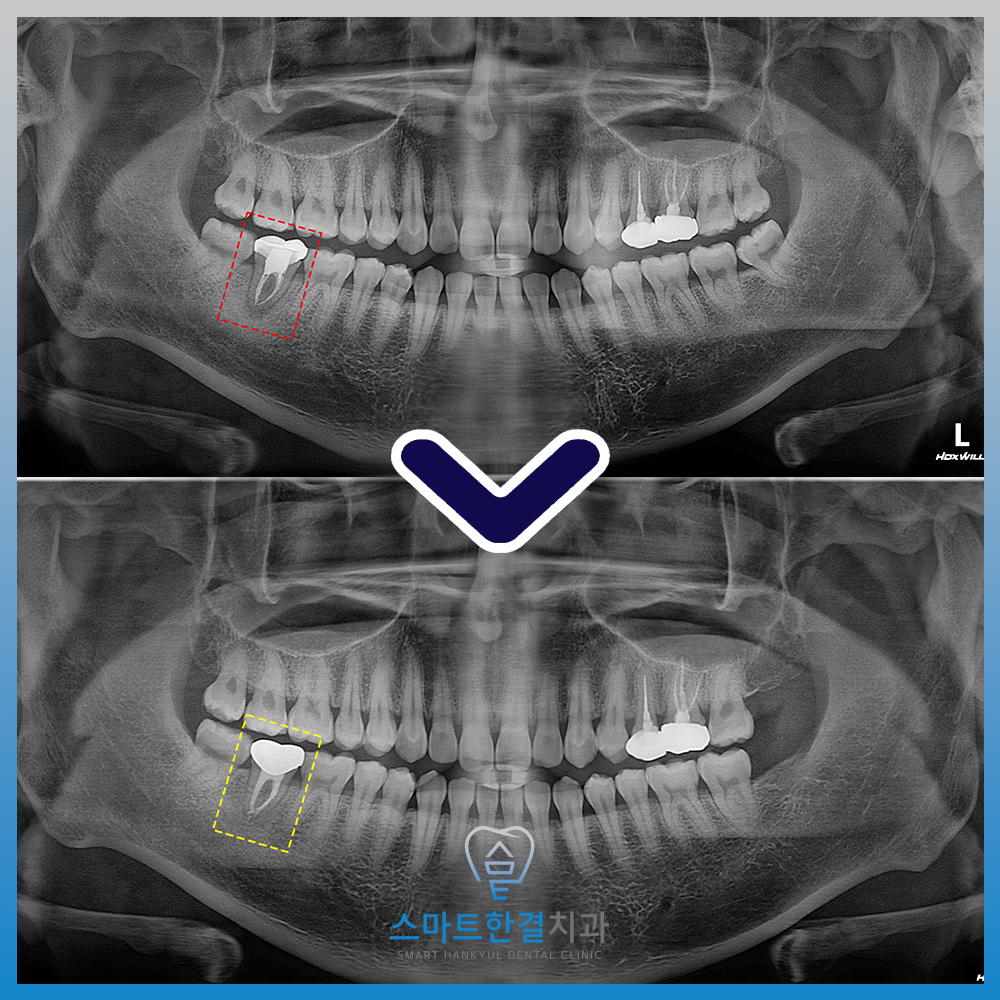

파노라마를 촬영하여 확인해 보니,

신경치료를 받았던 치아 뿌리로

염증이 잡혀있는 것을 확인할 수 있었어요.

위 사진은 신경치료 후

1년 8개월이 지난 사진으로

뿌리 끝 잡혀있던 병소도 전부 사라지고

증상도 없어졌어요.

화서동치과 스마트한결치과의

재신경치료 전후 사진이에요.